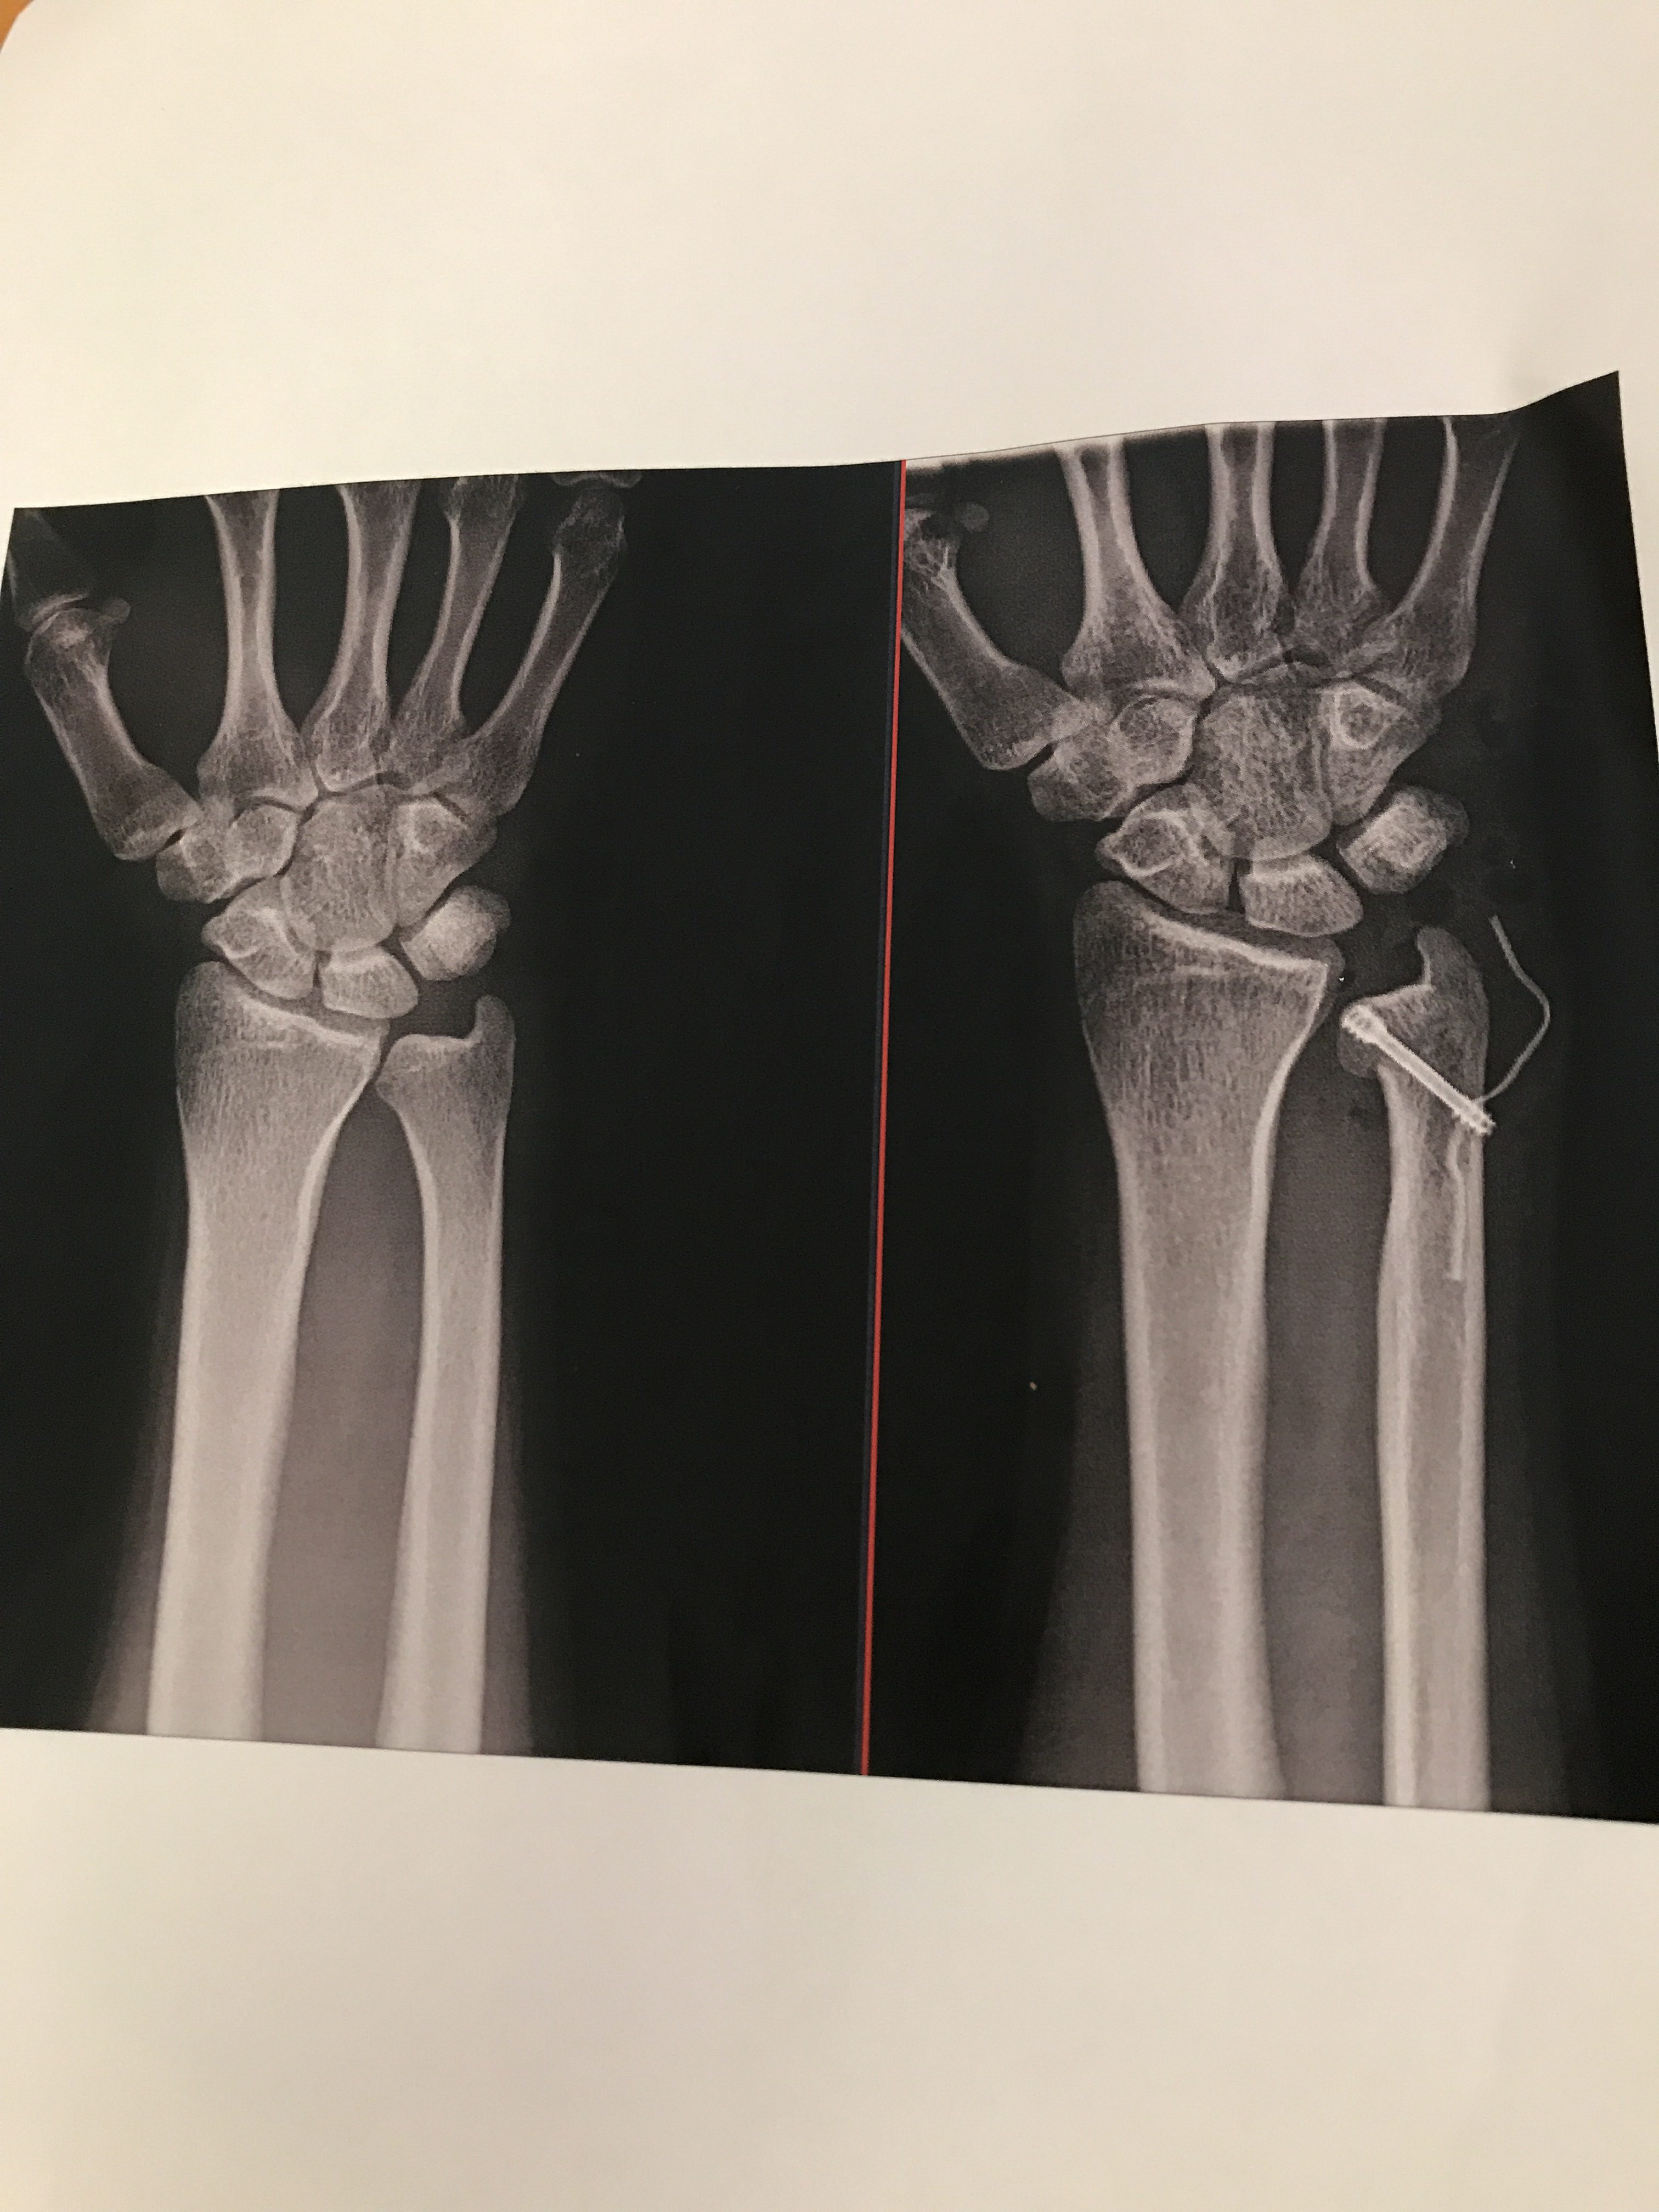

↓これが骨を切って短くしたレントゲン🤺🤺🤺

左が手術前で右が手術後です